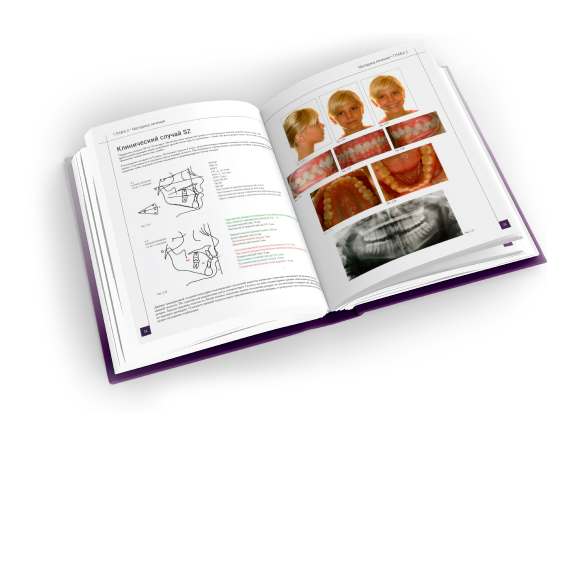

Корректор класса II Вильямса (исполнение 3) - Набор 320-0100

Описание товара

Характеристики